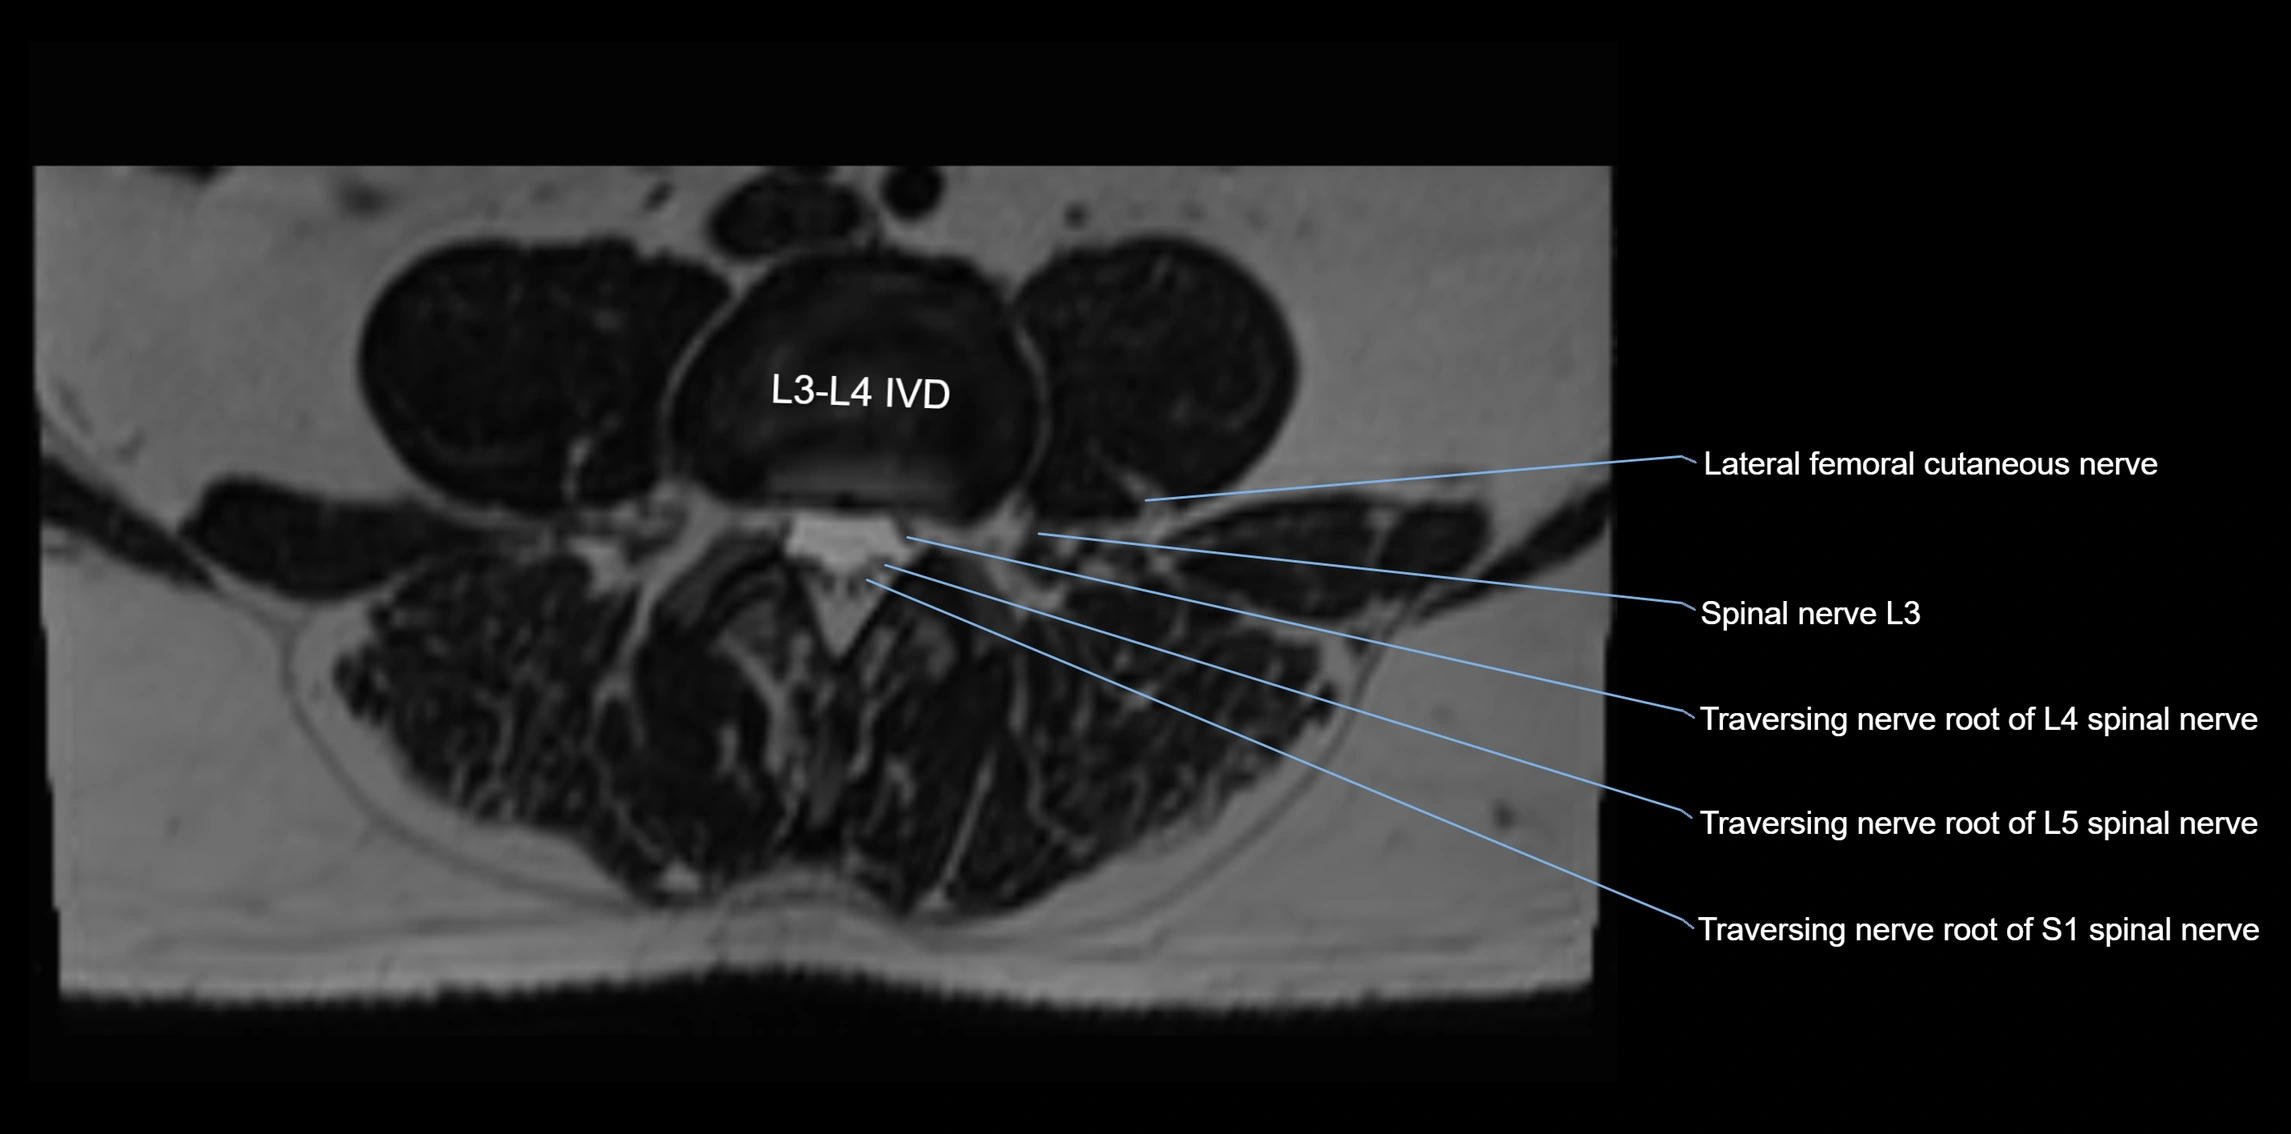

MRI image

image